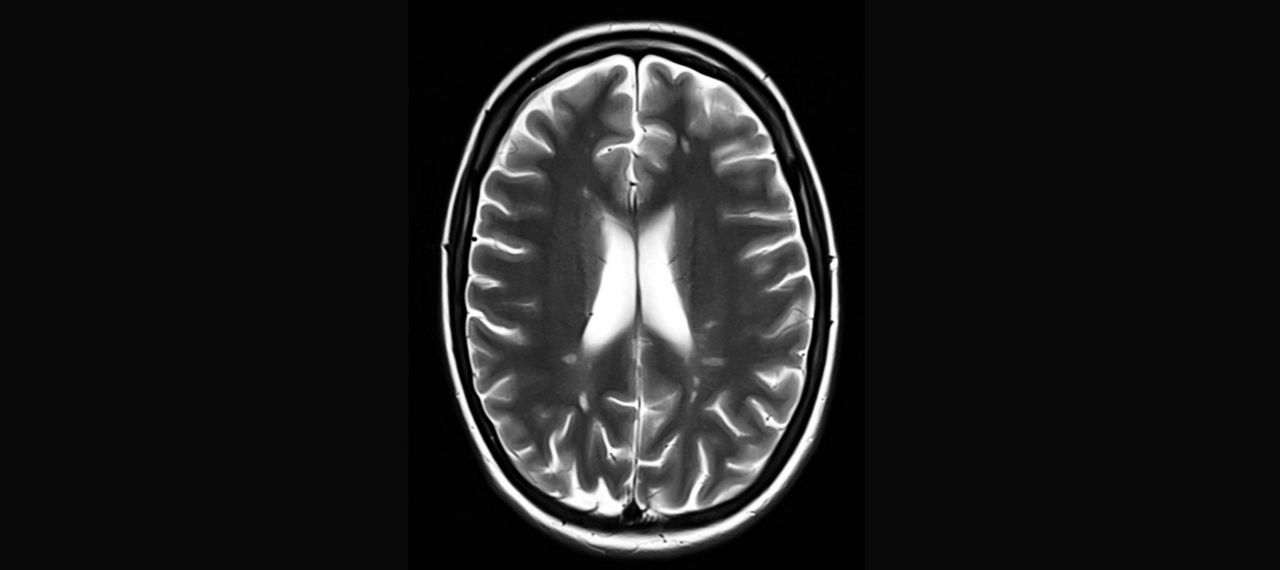

Abb.1: Periventrikuläre Läsionen in T2

Abb.2: T1+KM

Abb.3: PD

Herd im cervikalen Myelon: kurzstreckig, ungefähr 1 cm groß